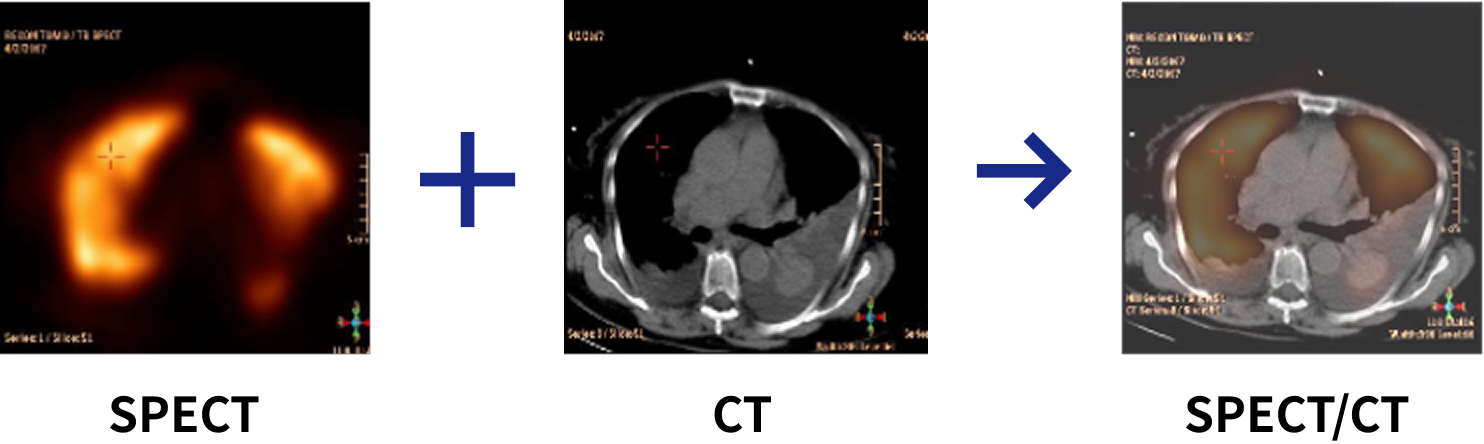

核医学装置とCTを組み合わせた「SPECT-CT装置」を導入しています。

核医学検査は、放射性医薬品を体内に投与し、その分布を画像化することで臓器の機能や代謝を評価できる検査です。

SPECT-CTでは、核医学画像に加えてCTによる解剖学的情報を融合することで、病変の正確な位置や性状を高精度に把握できます。

SPECT-CTの特徴

SPECTでは臓器や病変の「血流・代謝・集積状態」といった機能が分かり、CTでは正確な解剖学的位置や形状が把握できます。これらを重ね合わせることで、異常な集積が「どの部位にあるのか」「どの臓器や構造に一致するのか」が明確になり、腫瘍・炎症・虚血などの診断精度が向上します。